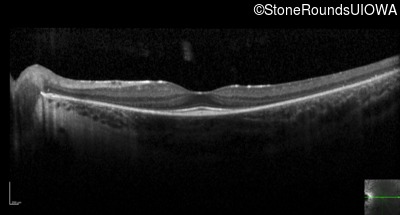

Optical Coherence Tomography - Left - 20/20 +2

Exemplar / OCT Stack